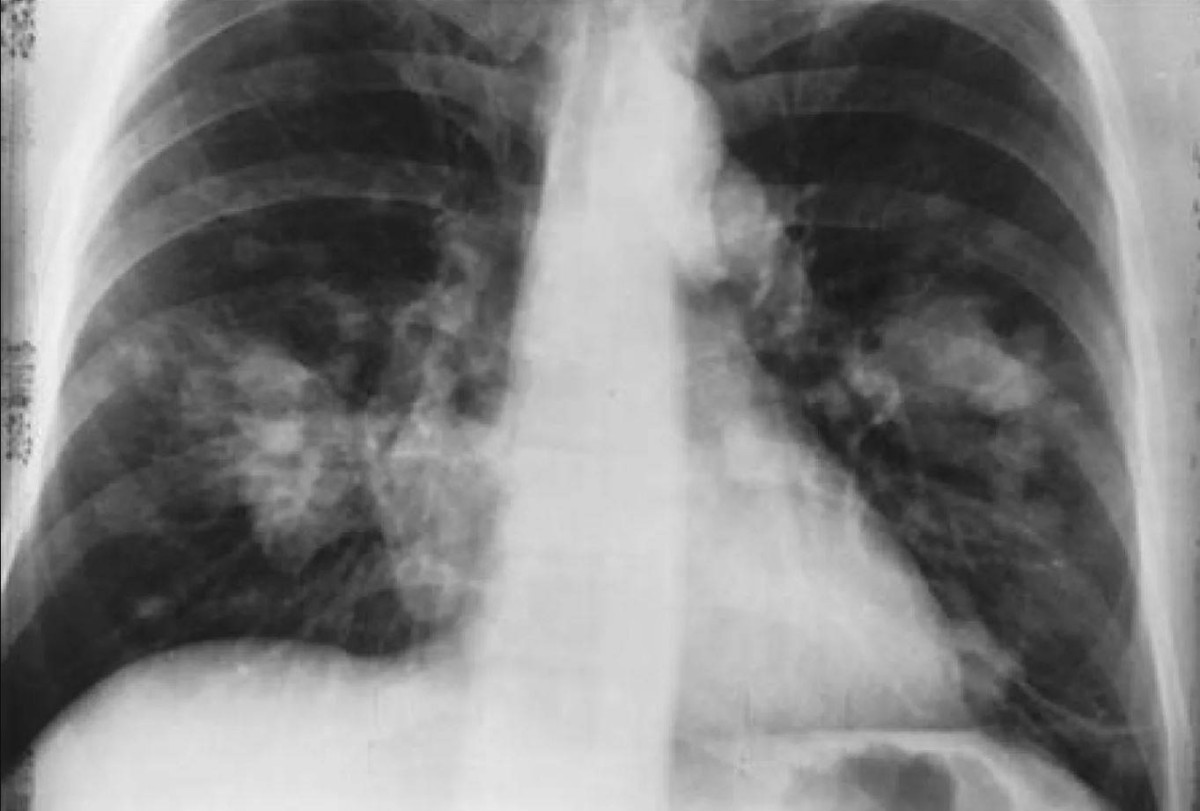

ربطت دراسات سابقة الالتهاب الناتج عن العدوى البكتيرية أو دخان السجائر بإعادة تنشيط خلايا السرطان الخاملة في الرئتين، لذا، أراد الفريق معرفة ما إذا كانت أمراض الجهاز التنفسي لها التأثير نفسه، لاختبار ذلك، أعطى الباحثون الإنفلونزا وفيروس كورونا المستجد (SARS-CoV-2) لفئران مُعدّلة وراثياً للإصابة بسرطان الثدي، ونتيجةً لذلك، بدأت خلايا السرطان الخاملة، التي انتشرت بهدوء إلى الرئتين، بالاستيقاظ.

لا يعلم العلماء ما إذا كان هذا هو نفس الوضع الذي يحدث عند إصابة الناجين من السرطان بأمراض الجهاز التنفسي، لكن الأدلة الأولية تشير إلى احتمالية ذلك، كشف تحليل لقاعدتي بيانات لمرضى السرطان عن وجود ارتباط كبير بين الوفاة المرتبطة بالسرطان وانتشار الورم في الرئتين بعد الإصابة بفيروس كورونا.

وفي مجموعة أخرى من مرضى سرطان الثدي تحديداً، زاد خطر إصابتهم بسرطان الرئة بنسبة تقارب 50% عند تشخيص إصابتهم بفيروس كورونا.